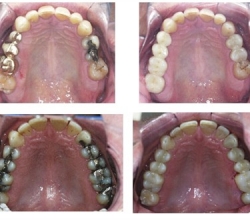

Inlays & Onlays